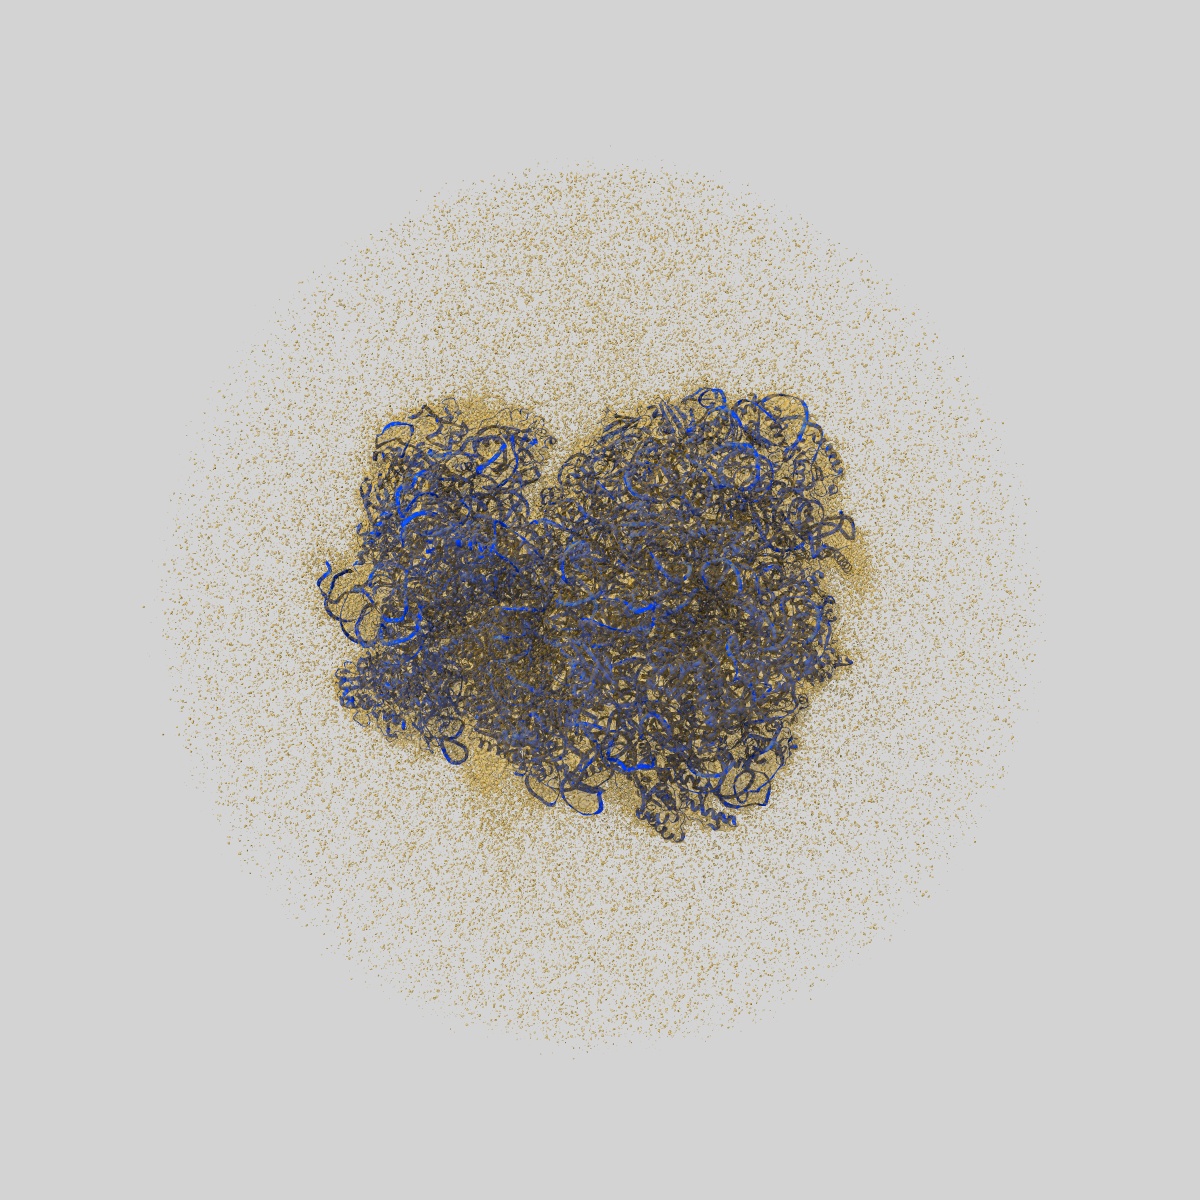

Cryo-EM map of the Candida albicans ribosome with tRNA-fMet, mRNA, and compounds (GEN and MFQ) with strong density for the P-site tRNA

Single-particle2.15 Å

Sample: Candida albicans ribosome in complex with initiator fMet-tRNA, mRNA, and GEN+MFQ

Mechanism of read-through enhancement by aminoglycosides and mefloquine.

(2025) PNAS , 122 , e2420261122 - e2420261122